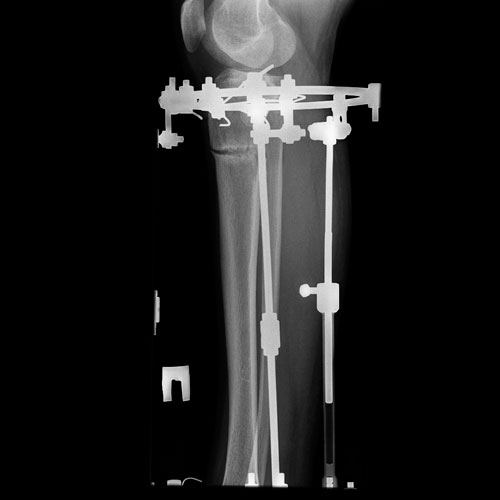

Исходник - 26 лет.

Дата операции 27.09.2016г.